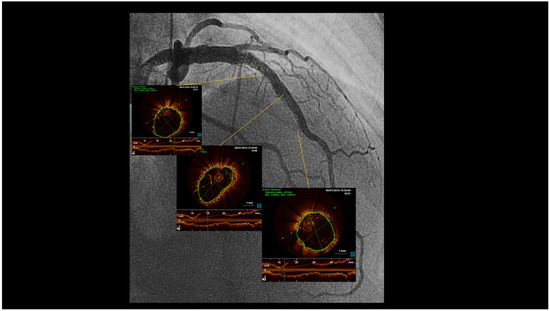

Fusiform Mid-LAD Aneurysm Due to Passive Arterial Wall Dilatation After Implantation of a Self-Expandable Stent